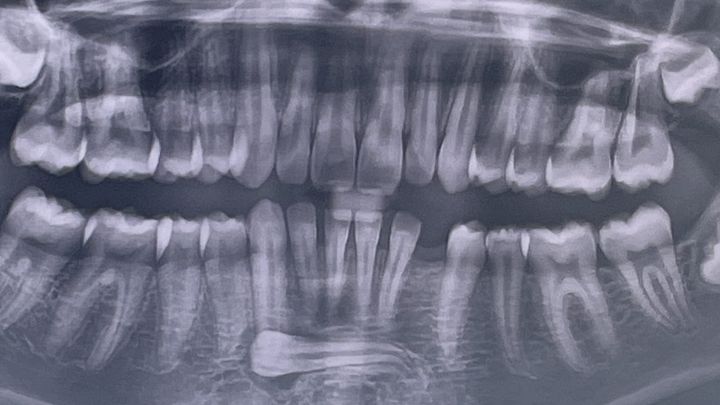

Hi, my name is Amber and I am raising funds for my son Justices oral surgery. We recently were told that one of justices adult teeth had turned sideways into his chin instead of emerging like a normal adult tooth would, as well as having an under developed lower jaw. Because of this he is now in need of oral surgery to remove the tooth that has turned along with all 4 wisdom teeth. Once his oral surgery is complete he will have to have 3 types of dental blocks/braces over 3 years, followed by upper and lower retainers night and day until he is 20 and then will need to have a dental implant placed.

If he does not have the surgery and braces started within the next year his lower teeth will push out of his lower jaw, and they will likely have to brake his jaw to help it grow instead.